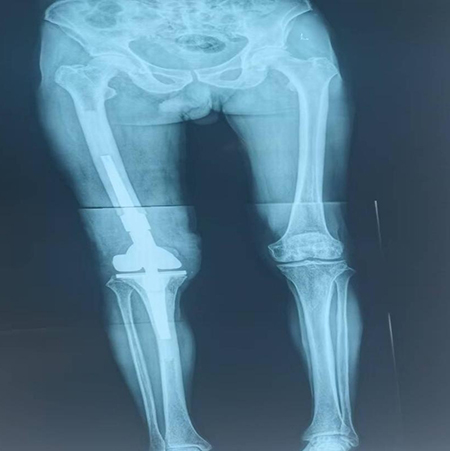

術(shù)后雙下肢全長(zhǎng)片